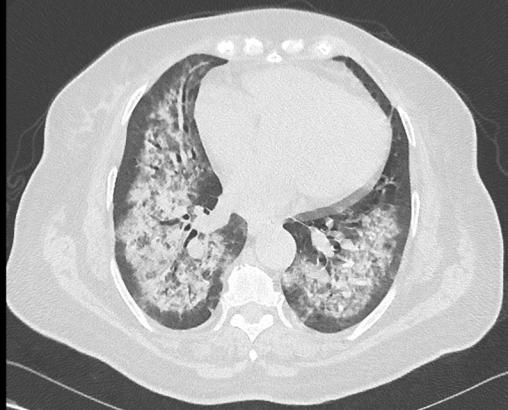

Étienne Crickx, La Revue du Praticien Scanner thoracique, coupe parenchymateuse. Opacités alvéolaires périhiliares, respectant les espaces sous pleuraux, bilatérales (hémorragie intra-alvéolaire).